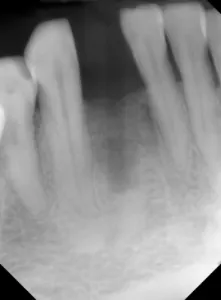

This is the case of a patient who has been missing a lower incisor for more than a year due to a failed root canal treatment (RCT). While there’s plenty of space mesiodistally, bone sounding helped us determine that there was only 4 mm of bone in the buccolingual dimension. A mini-implant was placed without raising a flap, the impression was taken at the time of surgery, and the implant was restored three weeks later.

Figure 1: Radiograph of pilot drill